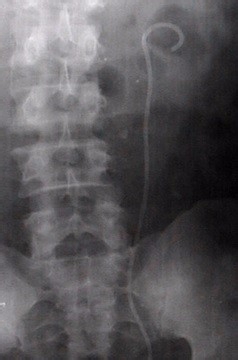

2、外科治疗:1、体外冲击波(震波)碎石;2、经皮肾镜 碎石术;3、开放式手术